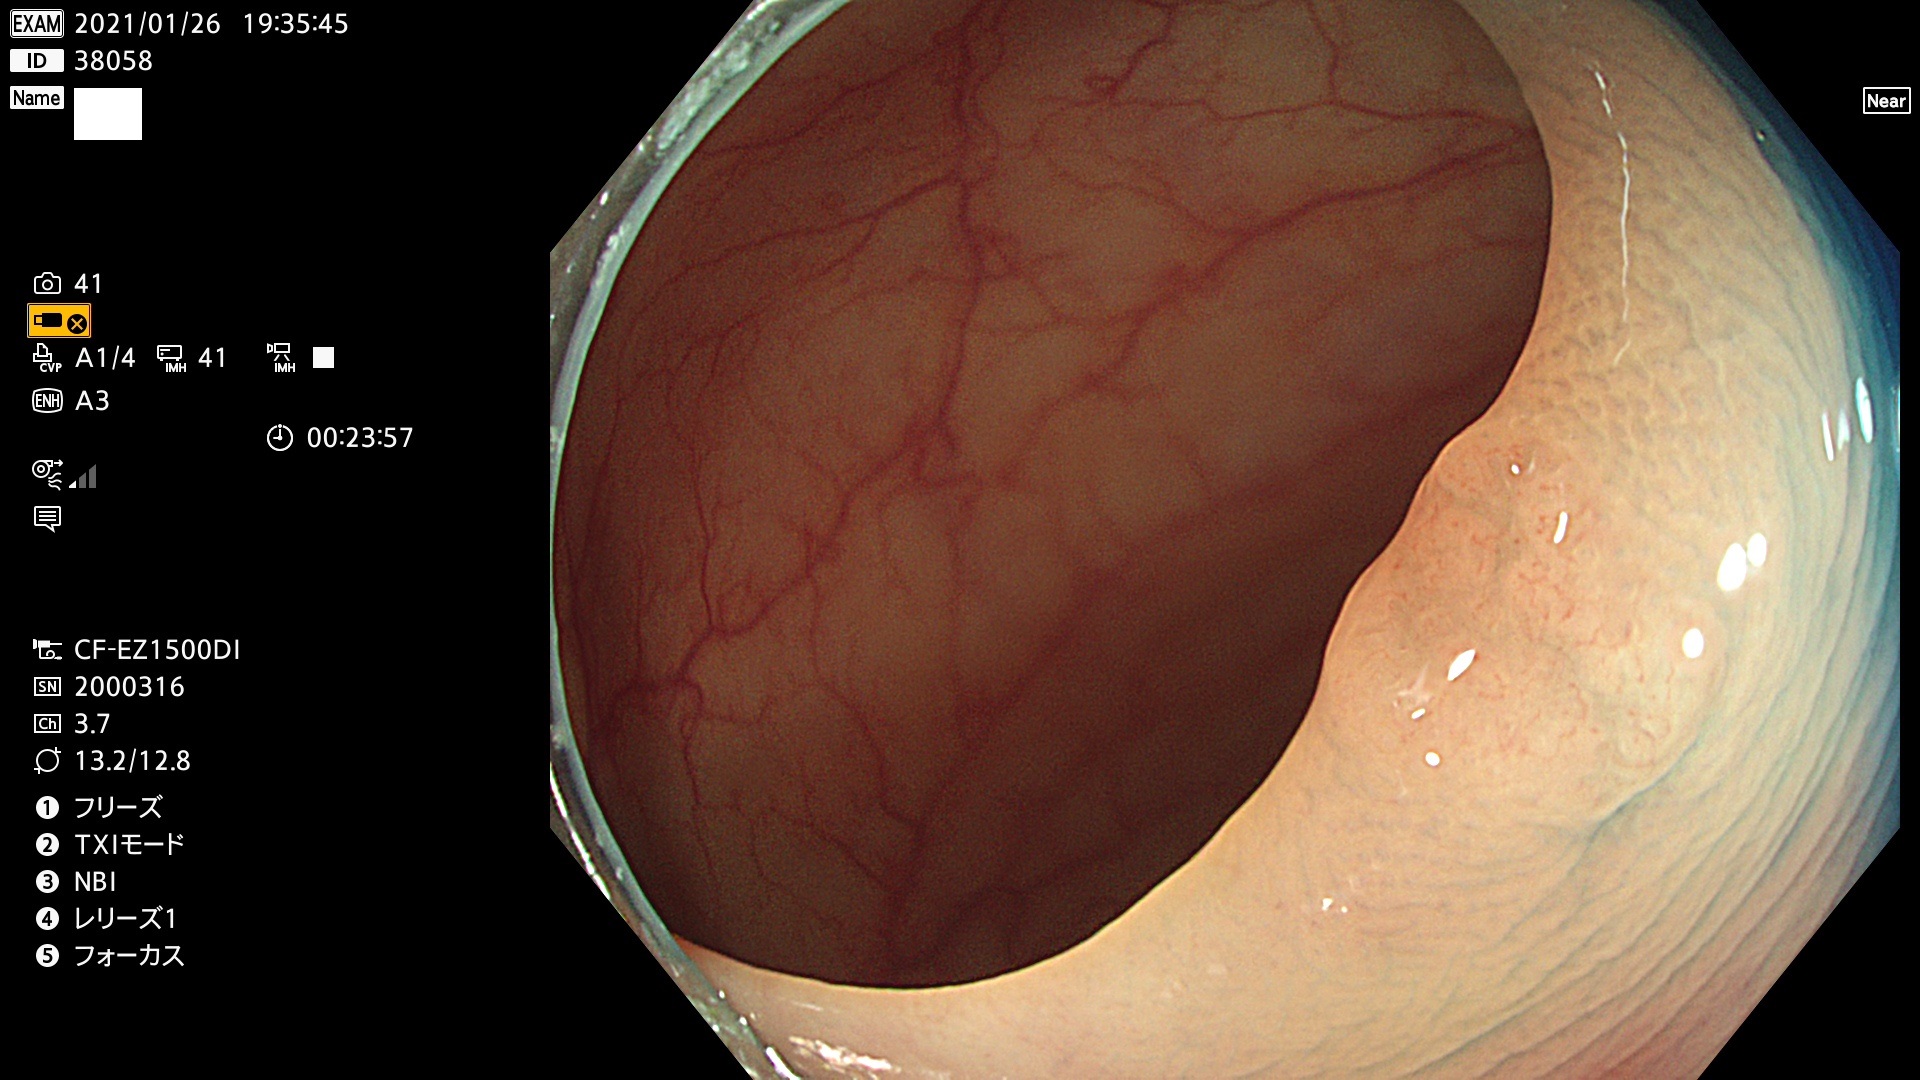

38001 38002 38003 38004 38006(SSAPのみ) 38007 38008 38009 38010 38012 38013 38014 38016 38018 38020 38021 38025 38026 38029 38032 38033 38034 38035 38036 38037(SSAPのみ) 38039 38043 38044 38048 38049 38050 38052 38055 38056 38057 38058 38059 38064(SSAPのみ) 38065 38068 38069 38070 38071 38072 38074 38075 38076 38078 38079 38080 38082 38083 38084 38085(SSAPのみ) 38086 38087 38088 38089 38090 38091 38092 38093 38094 38097 38098 38099

発見困難で危険性の高い平坦型病変(上記100名より抽出)